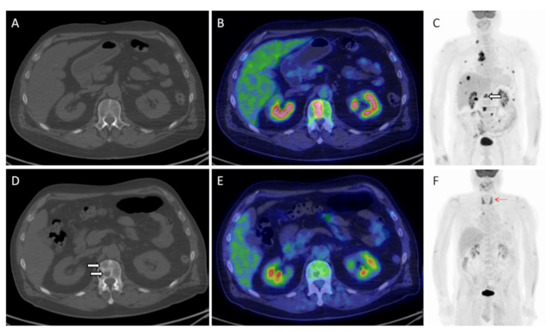

| Sachpekidis et al. | 2021 | prospective | melanoma | 25 | nivolumab, pembrolizumab, nivolumab plus ipilimumab | SUVmean, SUVmax and quantitative on dynamic PET (K1, k3, influx, FD, fractal dimension) | SUVmean, SUVmax and FD adversely affected PFS | [62] |

| Schank et al. | 2021 | retrospective | melanoma | 45 | nivolumab, pembrolizumab, ipilimumab, nivolumab plus ipilimumab | EORTC, PERCIMT | Two-year PFS was 94% among CMR patients and 62% among non-CMR patients | [63] |